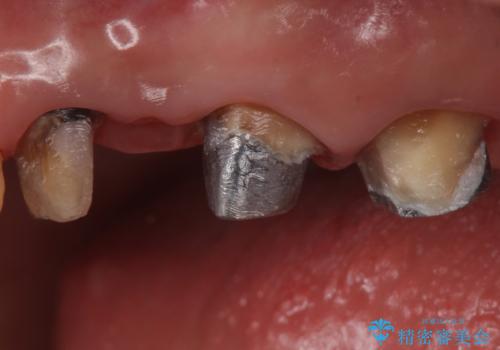

銀歯を除去し、土台の歯にに虫歯がないかを確認します。

今回は目立つ虫歯がなかったため、形を整えて白い被せものを装着しました。